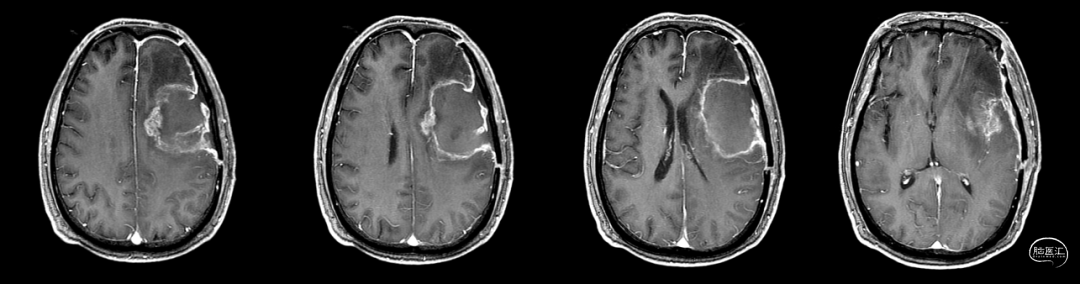

增强MR(外院),可见不均匀明显强化,中间可见不强化坏死区,边界不清:图示。

放疗后17月(2021-12-20)MRS显示左颞叶感兴趣区Cho/NAA约1.19-5.53:图示。

放疗后17月(2021-12-20)PWI显示感兴趣区脑血容量及血流量较对侧高低不一,平均通过时间及达峰时间延长,提示左侧病变区血流灌注降低:图示。

术后5周开始实施标准的新STUPP方案的辅助治疗,即在同步放化疗后,辅助替莫唑胺化疗的同时使用了电场治疗。目前生存25月,且临床和影像学表现均提示稳定,未见复发迹象。期间,在放疗后7月时复查MRI提示异常FLAIR信号区增大,经我院MDT讨论,考虑到强化信号减轻,无明显占位效应,患者无症状体征,考虑是治疗后水肿,非进展,故继续按原方案治疗。放疗后17月复查MRI出现术区边缘局部强化范围稍增大,但PWI示强化区局部呈低灌注且未见弥散受限表现,MDT讨论考虑为假性进展,继续原方案治疗。后续复查MRI强化范围减轻,证实了MDT的判断证实疾病稳定。患者生存时间已达25个月。全程安全顺利,仅出现一过性轻度皮肤反应。

辅助TMZ治疗过程中每2-3月复查MRI。治疗中曾出现水肿范围增大,尽管有部分区域弥散受限和MRS异常及血流量增加,但是临床症状未加重,仍继续原方案治疗,后续监测PWI显示病变区灌注减低。提示持续肿瘤电场治疗可以使病变长期稳定。此患者每天佩戴肿瘤电场治疗时间接近22小时,中间出现头皮发红和小水泡,经局部外用皮质类固醇和外用抗生素,暂停2天治疗恢复。至今随访25月稳定。说明肿瘤电场治疗联合TMZ治疗较单TMZ治疗明显延长胶质母细胞瘤患者PFS及OS,临床应积极推广使用。